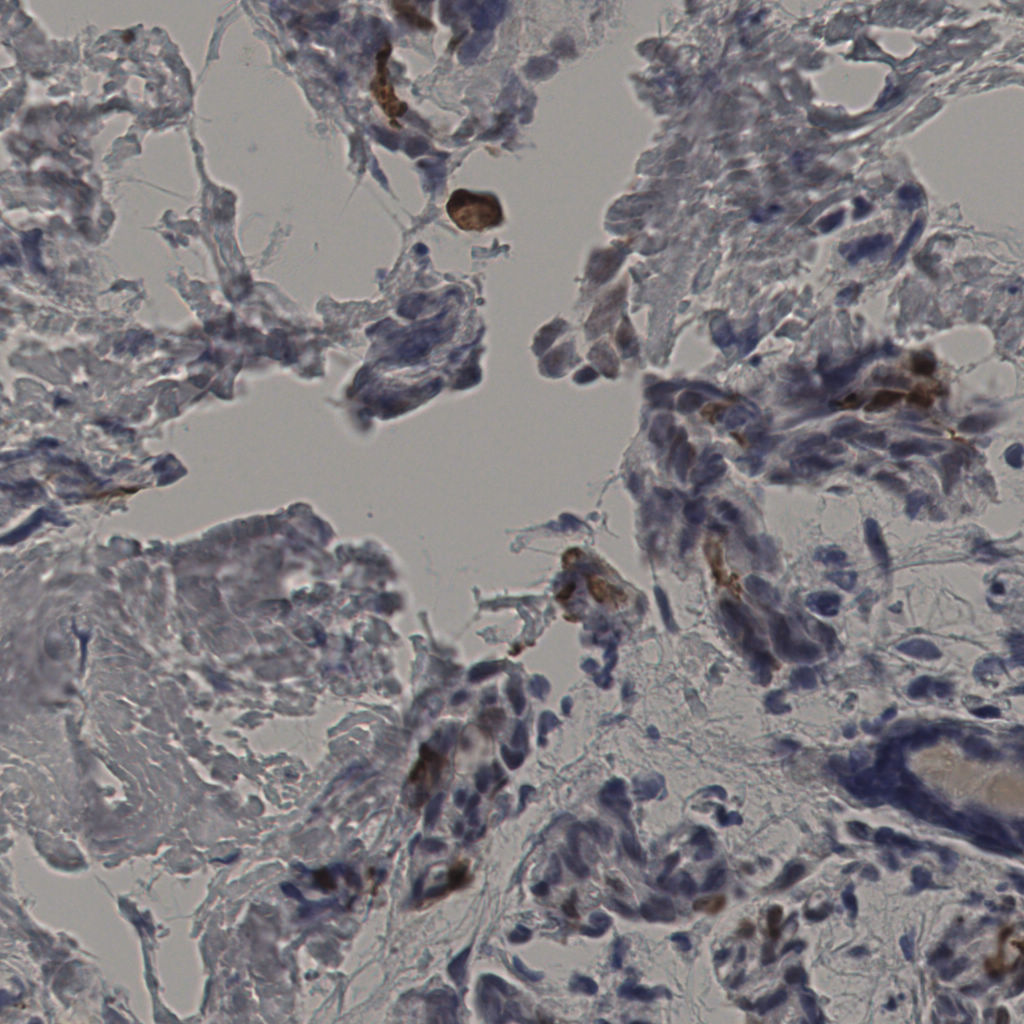

缩略图

标记后

标记前